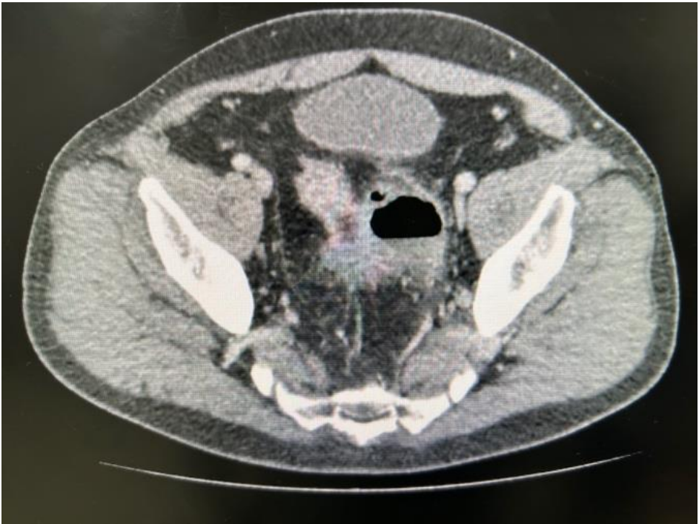

Paciente masculino de 56 anos, sabidamente portador de doença diverticular dos cólons, apresenta dor abdominal tipo cólica há 5 dias, com diminuição do apetite e procurou atendimento para investigação. Ao exame físico apresentava dor à palpação profunda em fossa ilíaca esquerda, sem massas palpáveis, com DB negativo.

Foram realizados exames laboratoriais: Hemoglobina: 12,6 g/dL, Leucócitos: 16.260/mm³, Plaquetas: 260.000/mm³, Creatinina: 1,2 mg/dL, Ureia: 21,8 mg/dL, PCR: 23,9 mg/L (VR: <1,0 mg/L).

Realizada tomografia computadorizada de abdome com contraste, mostrando imagem de coleção de 5,6cm de tamanho justa-cólico, sem pneumoperitônio livre, conforme imagem abaixo:

Qual deve ser a conduta inicial para esse paciente?